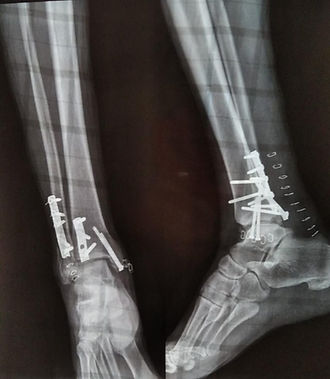

Una de las urgencias que pueden presentarse son las fracturas, estas son la ruptura total o parcial de un hueso. Puede ser producida por una caída, golpes fuertes o la contracción violenta de un músculo. Existen dos tipos: las cerradas, en las que el hueso se rompe y la piel permanece intacta, y aquellas en que la herida está abierta y el hueso fracturado se desplaza hacia el exterior.

Tienen mayor riesgo de padecer una fractura las personas con osteoporosis, aunque también llegan a ser frecuentes en niños y ancianos porque su composición ósea es más frágil.

Cada fractura necesita:

una evaluación individualizada

y un tratamiento ajustado al tipo que corresponda y a tu circunstancia personal

Puede que un tratamiento inicial pueda serte prescrito por cualquier profesional sanitario.

Pero el tratamiento definitivo y tu seguimiento te lo debe hacer un especialista en traumatología

las fracturas pueden tratarse de manera conservadora o quirúrgica.

Las operaciones de fracturas son muy variadas, tanto como los huesos y tipos que existen.

Los procedimientos pueden ir desde:

Intervenciones percutáneas, en las que apenas se hace una pequeña incisión en la piel y los cirujanos nos guiamos por las imágenes que muestra un aparato de escopia en quirófano

A operaciones donde son necesaria la reducción y colocación de distintos tipos de implantes e incluso una prótesis si se trata de una articulación.